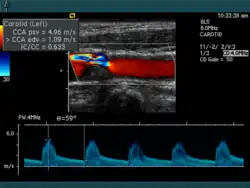

Die Aussagekraft der Sonografie kann erheblich durch die Anwendung des Doppler-Effekts erhöht werden. Man unterscheidet eindimensionale Verfahren (Pulsed-Wave-Doppler, Continuous-Wave-Doppler, auch als D-mode bezeichnet) von zweidimensionalen, farbkodierten Anwendungen (Farbdoppler – F-mode). Die Kombination B-Bild mit Pulsed-Wave-Doppler (PW-Doppler) nennt man auch Duplex.[4]

Doppler-Verfahren werden benutzt zur Bestimmung von Blutfluss-Geschwindigkeiten, zur Entdeckung und Beurteilung von Herz(klappen)fehlern, Verengungen (Stenosen), Verschlüssen oder Kurzschlussverbindungen (Shunts), siehe Farbkodierte Doppler-Sonografie.

Bei der farbkodierten Doppler-Sonografie wird für einen großen Bereich eines konventionellen Ultraschallbildes (Color-Window) die örtliche Doppler-Frequenz (= mittlere Flussgeschwindigkeit) und deren Schwankungsbreite bestimmt. Damit möchte man die Turbulenz der Strömung abschätzen. Aufgrund der statistischen Bewegungen der Streuteilchen ist die Schwankungsbreite der Fließgeschwindigkeit jedoch stets größer als die Turbulenz. Das Ergebnis wird in Falschfarben auf dem B-Bild überlagert, also in Farbtönen von rot und blau für verschiedene Blutgeschwindigkeit und grün für Turbulenz. Hierbei steht üblicherweise die Farbe Rot für Bewegung auf den Schallkopf zu, während mit blauen Farbtönen Flüsse weg von der Sonde codiert werden. Bereiche der Geschwindigkeit 0 werden durch die Elektronik unterdrückt.